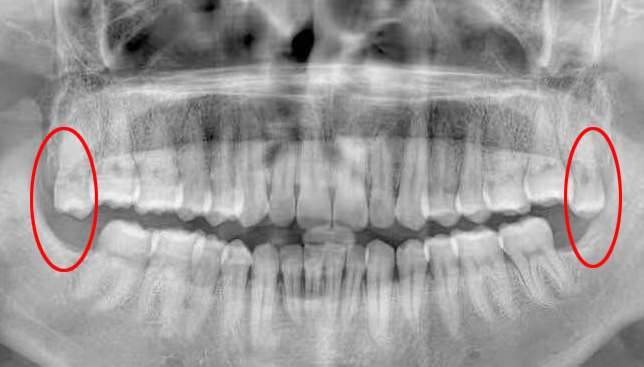

这种情况如果平时没有明显症状,一般要拍片才能发现,如下图:

如果上面长了、下面没长,或者下面长了、上面没长,那长出来的那颗就会更加放肆地过度萌出。这样一来,第二磨牙会被挤得更惨,对侧的牙龈和口腔黏膜也会跟着遭殃。如下图: